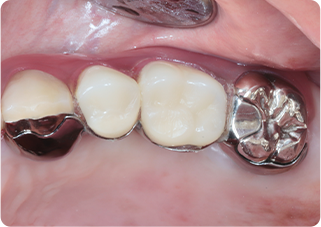

精密根管治療④

術前

術後

| 主訴 | 奥歯で噛むと痛い |

|---|---|

| 治療期間/回数 | 1ヵ月、3回 |

| 価格(税込) | 88,000円(税込) |

| リスク・副作用 | 病変再発、歯根破折の可能性 |

| ポイント | う蝕検知液を用い、むし歯の取り残しが無いようにし、ラバーダム防湿を行い、無菌的に根管治療を行った。根管充填材は、殺菌作用の強い保険適応外のMTAセメントを使用した。 |